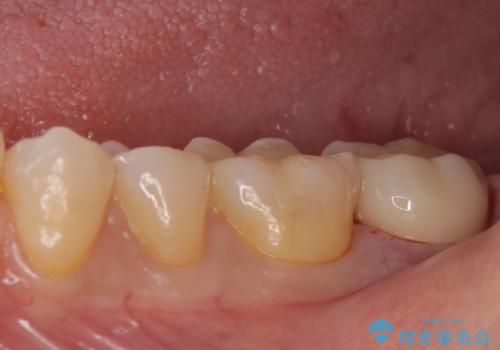

銀の詰め物が取れた。

- 銀の詰め物が取れたとのことで来院。

詰め物の下には虫歯がありました。

銀の詰め物はかなり昔に治療されたそうです。

銀の詰め物は虫歯の再発リスクが高く、歯に痛みが出てしまうと歯の神経の治療もしないとならなくなってしまいます。